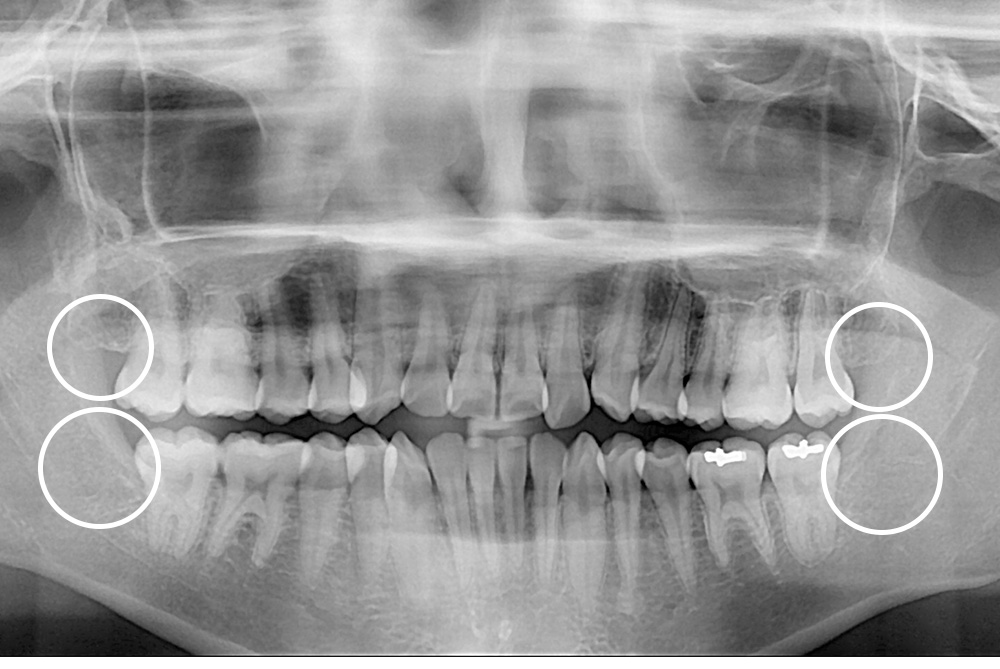

[사랑니] 매복 사랑니 발치

치료후 : 2019-09-14

세종치과는 구강악안면외과학 박사이신 원장님이 발치하는 치과입니다.